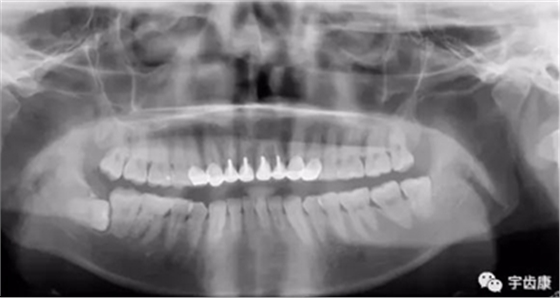

X線閱片知識(shí)